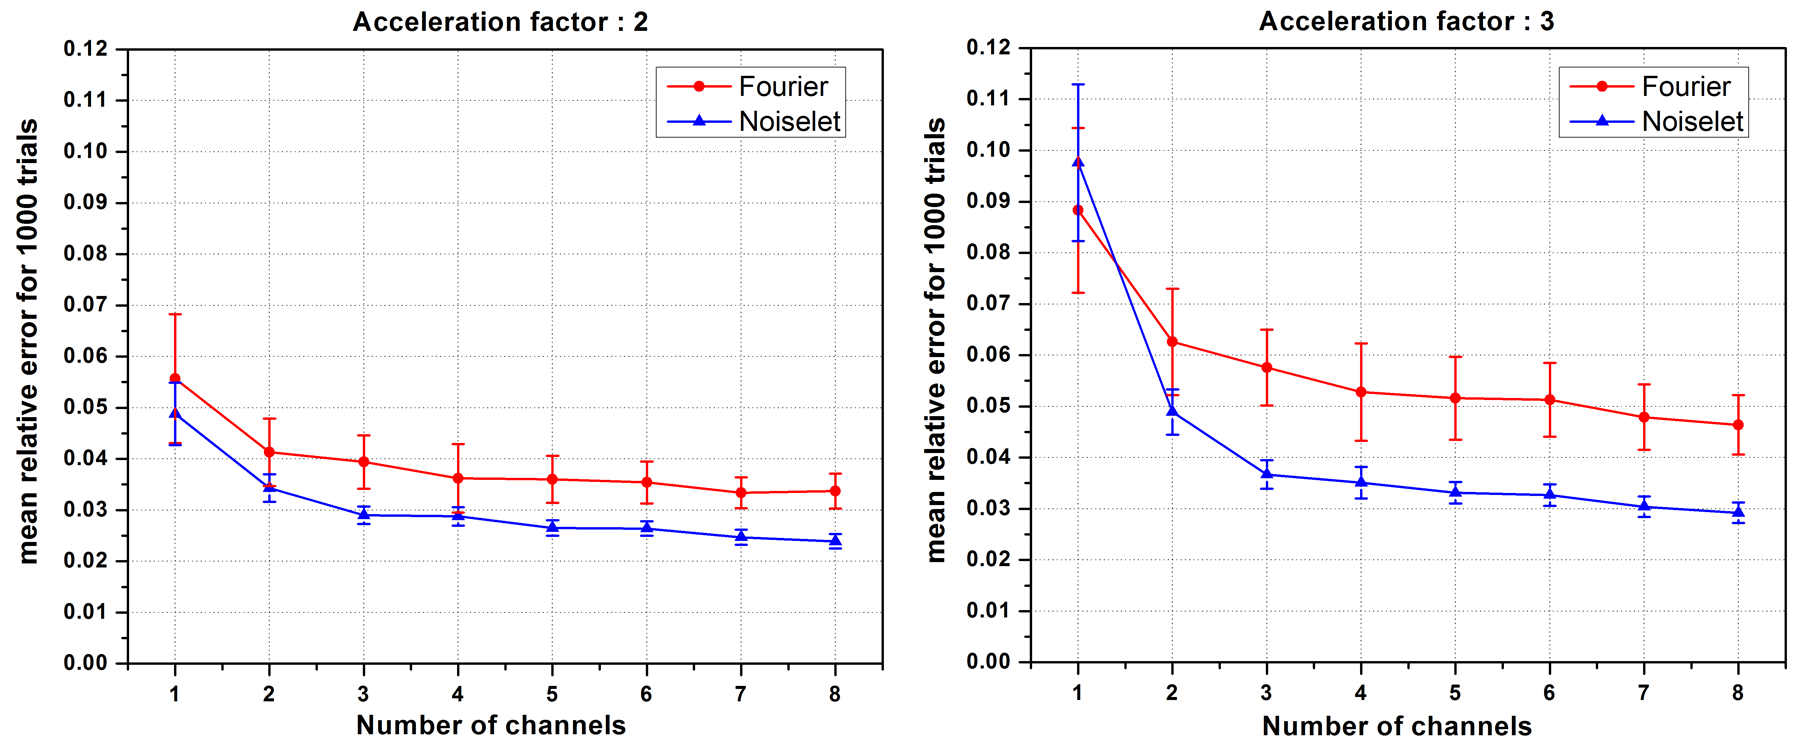

First we investigated the effect of the number of channels on the reconstruction quality using the MCS framework. For a fixed number of measurements, the number of channels was varied and the mean of the relative error for 1000 such simulations was calculated. Fig. 6 shows the plot of the mean relative error versus the number of channels for the acceleration factors of 2 and 3. When the number of channels was two, the noiselet encoding scheme outperformed the Fourier encoding scheme for both the acceleration factors of 2 and 3. However, when number of channels was equal to one, the noiselet encoding outperformed the Fourier encoding for an acceleration factor of 2, but not for an acceleration factor of 3. It is interesting to note that noiselet encoding outperformed Fourier encoding for both acceleration factors when the number of channels was greater than one. These simulations suggest that noiselet encoding should take into account the sensitivity information while performing CS, and therefore noiselet encoding is potentially a better encoding scheme for MCS-MRI. Based on the fact that noiselet encoding performs better than Fourier encoding for multi-channel data, we investigated the performance of both the encoding schemes using muti-channel data.